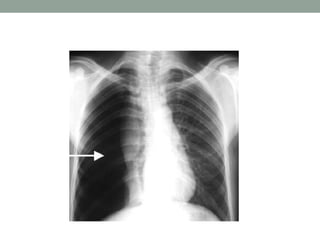

XQUANG

• Chủ yếu là những hình mờ chiếm một vùng hoặc rải rác

trên phế trường -> chiếm một phân thuỳ, hay một bên

phổi.

• Mật độ hình mờ có thể đều hoặc không đều, ranh giới rõ

rệt hoặc không.

• Ngoài ra còn phải quan sát các tạng lân cận: một hình mờ

lớn ở một bên phổi kèm theo co rút cơ hoành, trung thất

và các khoảng liên sườn -> đông đặc co rút.

• Nếu các tạng lân cận bị đẩy -> đó là tràn dịch màng phổi.